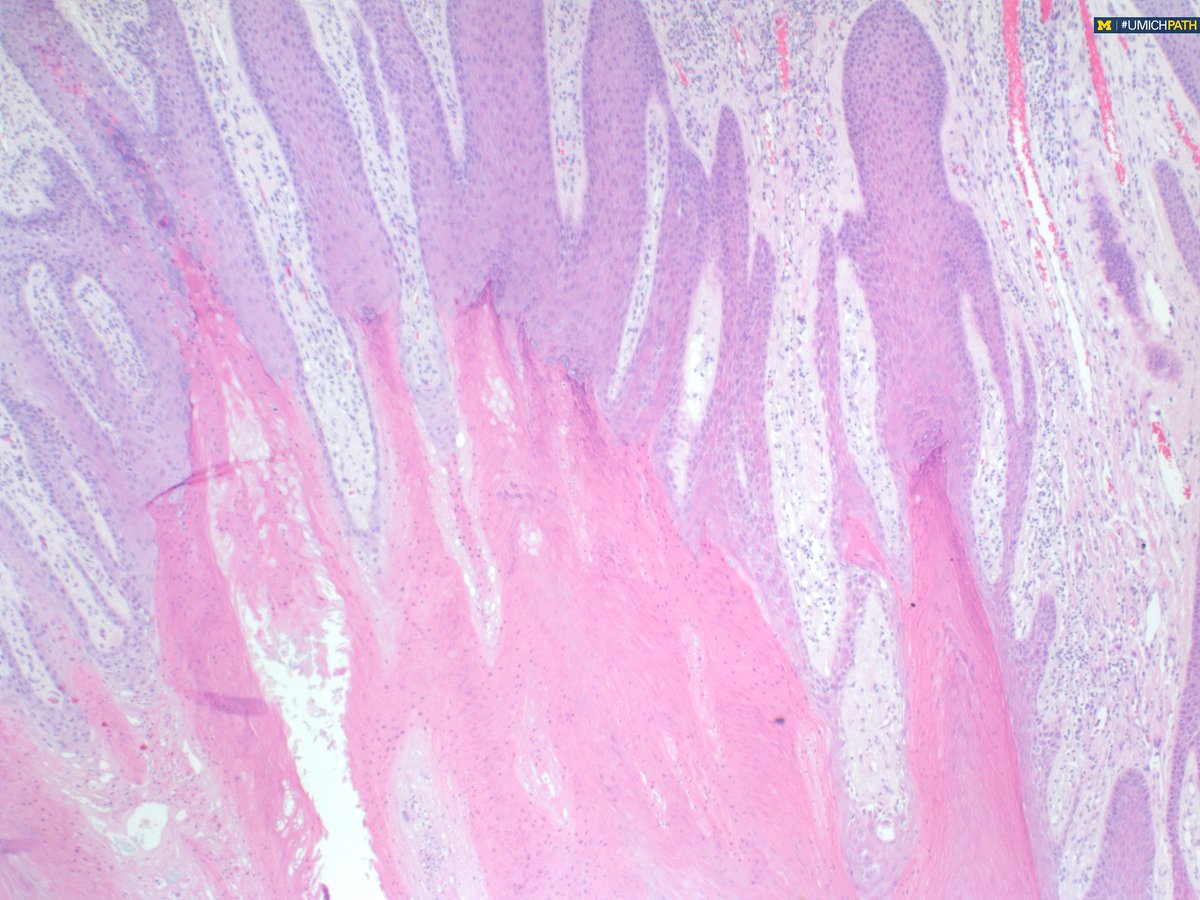

Answer:  This is a porokeratoma! At low power you see diffuse wave-like, columnar cornoid lamella with an abrupt transition from normal. Read more about this entity here: onlinelibrary.wiley.com/doi/10.1111/cu…

#COTW with PGY1 @meredithkherman featuring a variant in #dermpath.  Shave biopsy of groin lesion. What histologic features do you see? What is your differential diagnosis?

UMichPath's tweet image. #COTW with PGY1 @meredithkherman featuring a variant in #dermpath.  Shave biopsy of groin lesion. What histologic features do you see? What is your differential diagnosis?